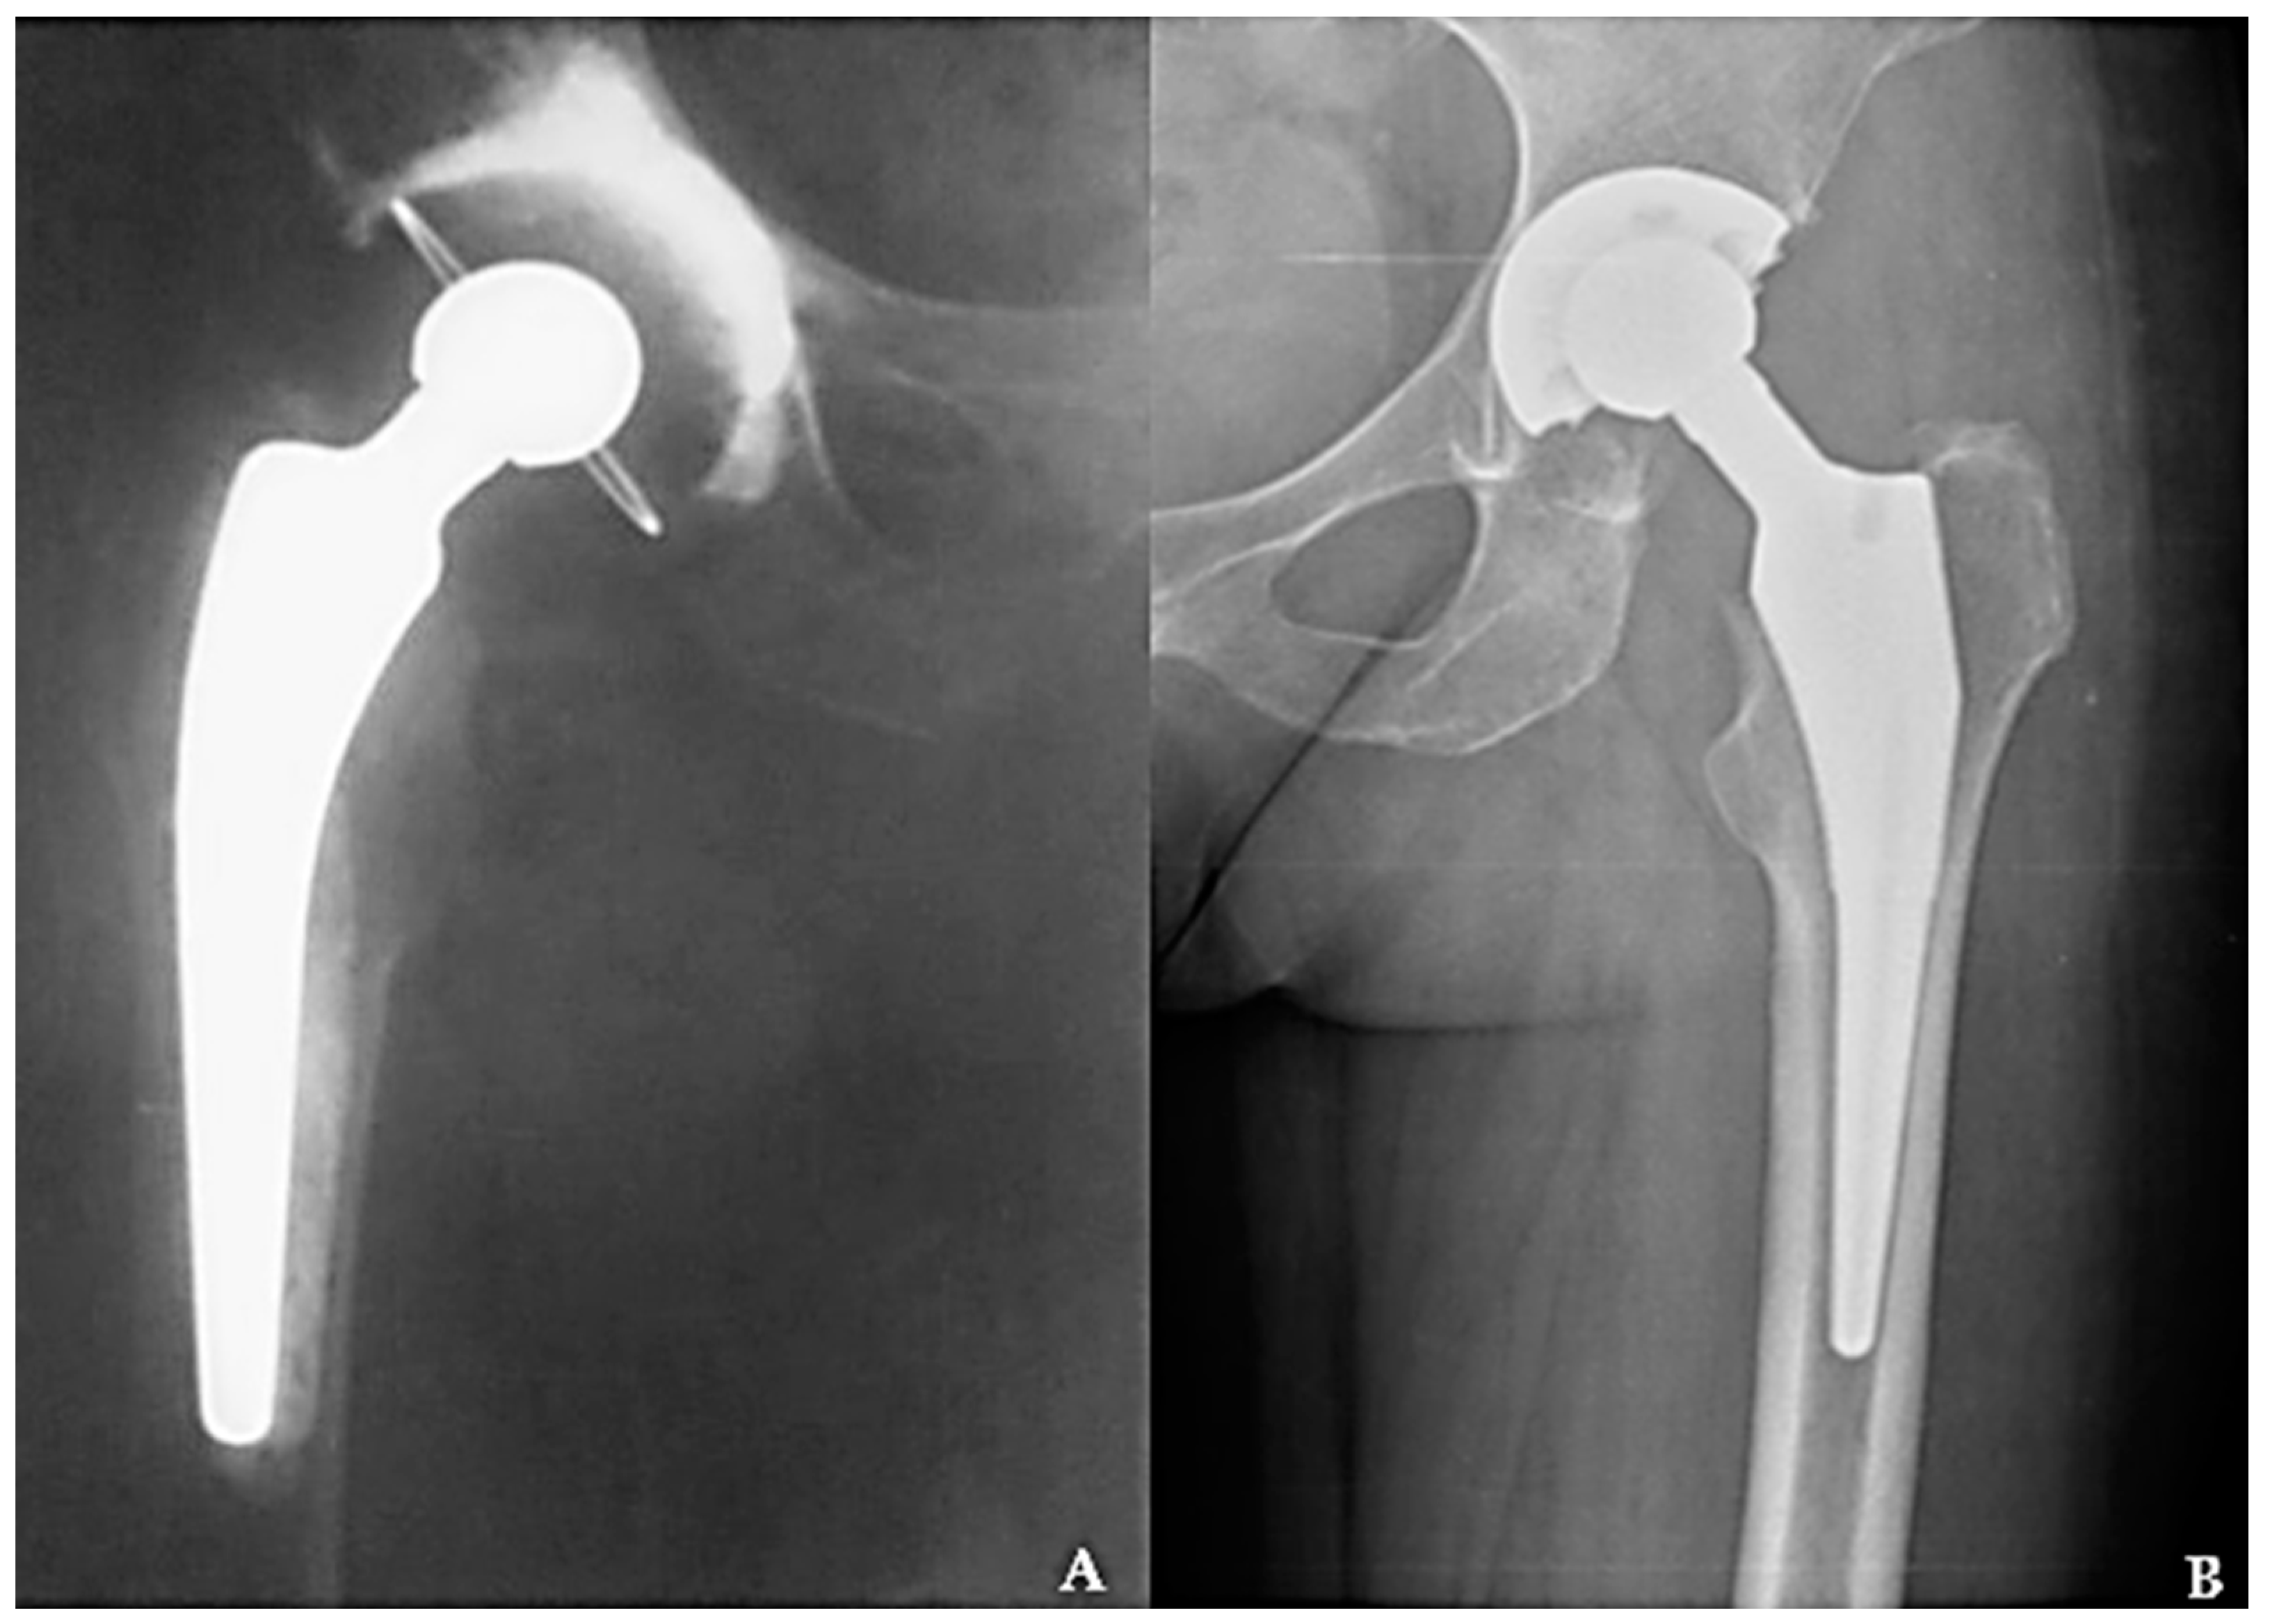

In orthopedic surgery, CHP is recommended mostly in elderly patients with associated comorbidities who suffer from osteoporosis in an advanced stage [19,20]. Due to the cementation, these prostheses have the advantage that they attach very well to the bone from the beginning (primary fixation) and allow full weight support on the treated leg, even from the first day after the prosthetic operation. The schematic representation of a CHP and the aspect of solidified polymeric cement in electronic microscopy are illustrated in Figure 1, and its radiographic aspect in Figure 2A, in comparison to a CLHP (B).

Figure 2. Total hip arthroplasty with CHP (A), versus a CLHP (B).